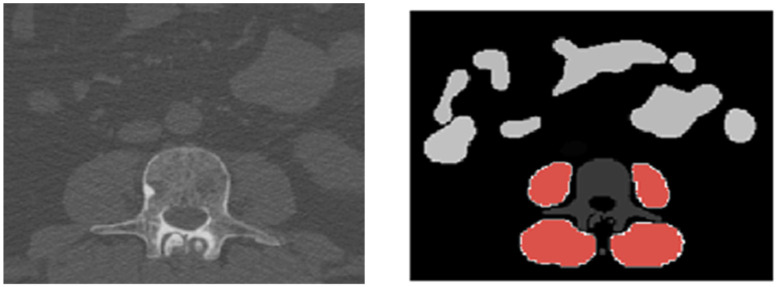

背景:肌肉减少症的特征是肌肉质量和力量的减少,导致功能限制和跌倒、受伤和骨折的风险增加。本研究的目的是获得多发性骨髓瘤(MM)患者在治疗期间骨骼肌变化的详细信息。方法:回顾性分析51例诊断为MM的患者,在诱导治疗(T1)和自体干细胞移植(T2)前接受了全身低剂量计算机断层扫描。利用全自动TotalSegmentator和体成分分析相结合的BOA工具生成的掩模,评估原位背部肌肉、髂腰肌和臀肌的总体积(TV)、肌肉体积(MV)和肌内脂肪组织体积(IMAT)。使用内部训练的人工智能网络获得全自动三维分割评估。结果:患者中位年龄58岁(IQR 52-66),男性38例,随访时间平均为11.8个月(SD±3)。MV和IMAT的变化与身体质量指数(BMI)显著相关(r = 0.7, p < 0.0001)。BMI下降(平均-2.2 kg/m2)的患者(n = 28)在治疗期间失去了MV (T1: 3419 cm3, IQR 3176-4000 cm3 vs. T2: 3226 cm3, IQR 3014-3662 cm3, p < 0.0001),而BMI增加(平均+1.4 kg/m2)的患者(n = 20) IMAT增加(T1: 122 cm3, IQR 96.8-202.8 cm3 vs. T2: 145.5 cm3, IQR 115-248 cm3, p = 0.0002)。不同肌群的MV损失不同,其中髂腰肌(-9.8%)、臀大肌(-9.1%)、臀中肌(-5.8%)、臀中肌(-4.3%)、臀小肌(-1.5%)的MV损失最为突出。体重增加的患者的IMAT增加在肌肉群之间是相似的。结论:基于人工智能的三维分割过程是一种可靠且节省时间的方法,可以获得MM患者肌少症的深入信息。MV的丧失和IMAT的增加可以可靠地检测到,并与BMI的变化相关。MV损失在2型肌纤维较多的肌肉(快速抽搐,高能量)中最高,而以1型肌纤维为主的肌肉(缓慢抽搐,姿势控制)受影响较小。这项研究为MM患者在治疗期间的肌肉变化提供了有价值的见解,这可能有助于更精确地根据患者的需要定制运动干预措施。

Background: Sarcopenia is characterized by a loss of muscle mass and strength, resulting in functional limitations and an increased risk of falls, injuries and fractures. The aim of this study was to obtain detailed information on skeletal muscle changes in patients with multiple myeloma (MM) during treatment. Methods: A total of 51 patients diagnosed with MM who had undergone whole-body low-dose computed tomography acquisition prior to induction therapy (T1) and post autologous stem cell transplantation (T2) were examined retrospectively. Total volume (TV), muscle volume (MV) and intramuscular adipose tissue volume (IMAT) of the autochthonous back muscles, the iliopsoas muscle and the gluteal muscles were evaluated on the basis of the resulting masks of the BOA tool with the fully automated combination of TotalSegmentator and a body composition analysis. An in-house trained artificial intelligence network was used to obtain a fully automated three-dimensional segmentation assessment. Results: Patients' median age was 58 years (IQR 52-66), 38 were male and follow-up CT-scans were performed after a mean of 11.8 months (SD ± 3). Changes in MV and IMAT correlated significantly with Body-Mass-Index (BMI) (r = 0.7, p < 0.0001). Patients (n = 28) with a decrease in BMI (mean -2.2 kg/m2) during therapy lost MV (T1: 3419 cm3, IQR 3176-4000 cm3 vs. T2: 3226 cm3, IQR 3014-3662 cm3, p < 0.0001) whereas patients (n = 20) with an increased BMI (mean +1.4 kg/m2) showed an increase in IMAT (T1: 122 cm3, IQR 96.8-202.8 cm3 vs. T2: 145.5 cm3, IQR 115-248 cm3, p = 0.0002). Loss of MV varied between different muscle groups and was most prominent in the iliopsoas muscle (-9.8%) > gluteus maximus (-9.1%) > gluteus medius (-5.8%) > autochthonous back muscles (-4.3%) > gluteus minimus (-1.5%). Increase in IMAT in patients who gained weight was similar between muscle groups. Conclusions: The artificial intelligence-based three-dimensional segmentation process is a reliable and time-saving method to acquire in-depth information on sarcopenia in MM patients. Loss of MV and increase in IMAT were reliably detectable and associated with changes in BMI. Loss of MV was highest in muscles with more type 2 muscle fibers (fast-twitch, high energy) whereas muscles with predominantly type 1 fibers (slow-twitch, postural control) were less affected. This study provides valuable insight into muscle changes of MM patients during treatment, which might aid in tailoring exercise interventions more precisely to patients' needs.